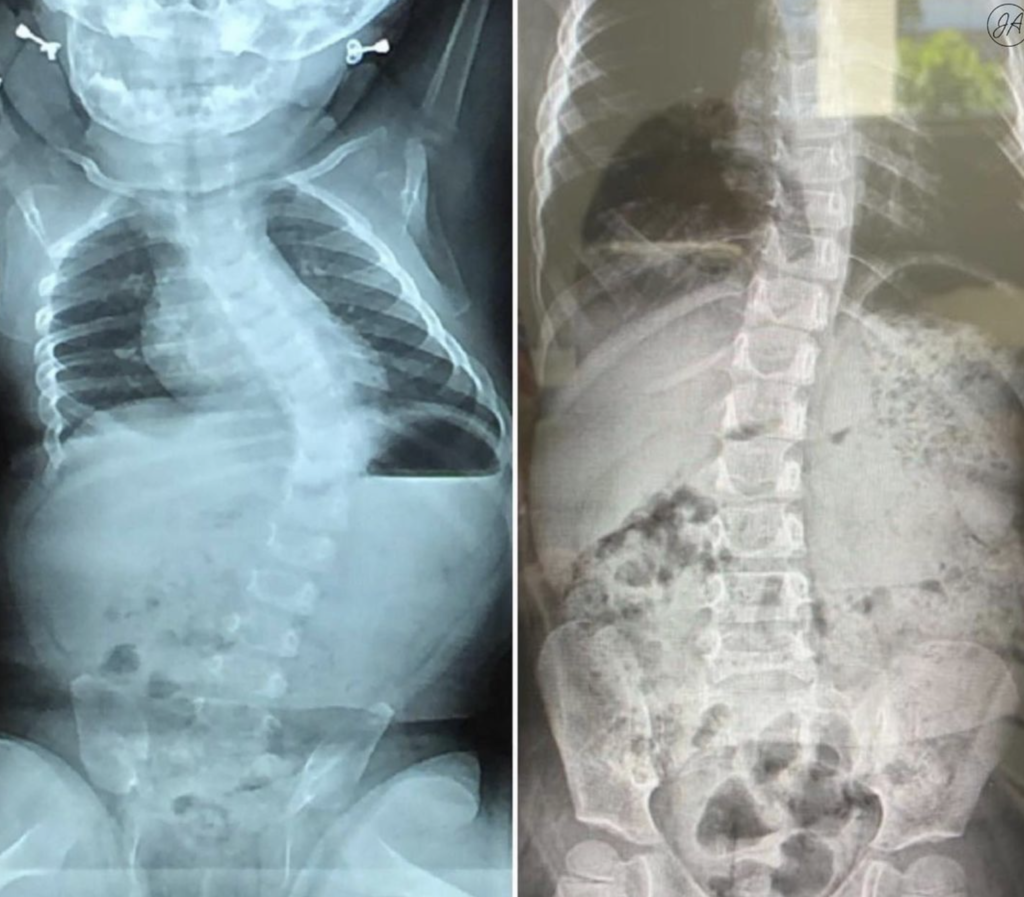

Bracing For Scoliosis

Scoliosis can be treated in many ways, but bracing is one of the oldest and tried-and-tested methods. Bracing requires a patient to wear a brace around their upper body to prevent a scoliotic curve from worsening. While bracing will not correct a scoliotic curve, it can effectively keep the Cobb angle, the standard used to […]